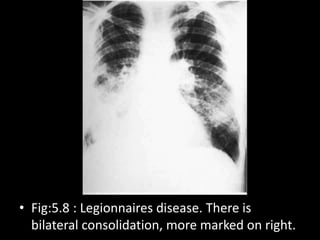

• Fig:5.8 : Legionnaires disease. There is

bilateral consolidation, more marked on right.

• Fig:5.8 :Legionnaires disease. There is bilateral consolidation, more marked on right.